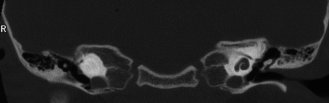

Figure 1. Labyrinthitis ossificans. The cochlea on the left shows obliteration by bone after meningitis. The scala tympani of the cochlea on the right was patent and the patient underwent successful implantation with complete electrode insertion.

Figure 1 shows the CT of a child deafened by meningitis whose left cochlea is ossified. In this child's case, successful implantation of the patent right cochlea was accomplished. For patients at risk of labyrinthitis ossificans, implantation at the time early ossification or fibrosis is identified may be indicated. Implant teams may follow patients newly deafened by meningitis with serial imaging and implant at the first sign of replacement of the scala tympani with fibrous tissue or bone. Otherwise, implantation in cases of post-meningitic deafness is usually recommended after a six-month period to allow for the possible recovery of aidable hearing in at least one ear.